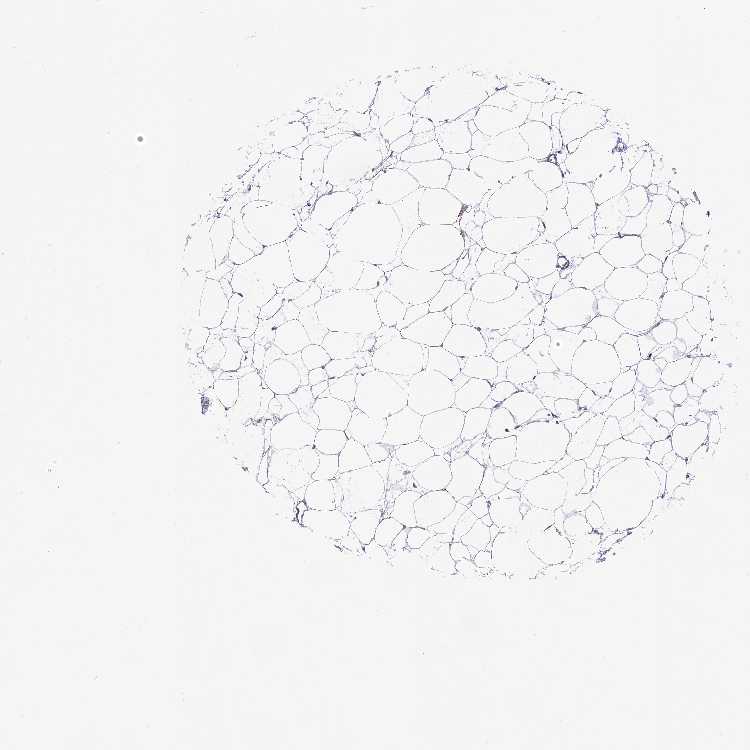

SOFT TISSUE 1 - Antibody stainingi

Antibody staining in the annotated cell types in the current human tissue is reported as not detected, low, medium, or high, based on conventional immunohistochemistry profiling in selected tissues. This score is based on the combination of the staining intensity and fraction of stained cells.

Each image is clickable and will lead to virtual microscopy that enables deeper exploration of all samples and also displays staining intensity scores, fraction scores and subcellular localization as well as patient and tissue information for each sample.

Antibody HPA043175Antibody HPA054868

Chondrocytes -Medium

Fibroblasts MediumNot detected

Peripheral nerve -Not detected